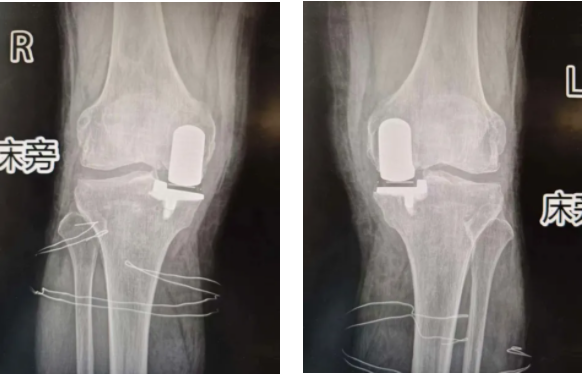

近日,西安医学院第一附属医院骨科一病区在副主任医师孙甫的主刀下,顺利为一位78岁的患有双侧骨性关节炎的患者,同期实施了双侧膝关节单髁置换术。此次手术不仅标志着西安医学院第一附属医院在关节置换领域实现了双侧同时置换“零的突破”,更以微创、保功能等特点,为高龄关节疾病患者提供了更优治疗选择,显著提升了其术后生活质量。

78岁高龄的周大爷(化名),长期受双侧膝关节疼痛、活动受限困扰,确诊为双侧骨性关节炎。传统的人工全膝关节置换创伤相对较大,且若分次进行双侧手术,患者将面临两次麻醉、两次康复的过程,身心负担沉重。经多学科MDT讨论,严谨评估,并与患者及家属充分沟通后,骨科一病区团队决定为其施行目前国际推崇的微创单髁置换术,并创新性地同期完成双侧手术。

在孙甫及团队的精细操作下,整个手术过程顺利,仅用时1.5小时。术后第二天患者便可以自行扶助行器下床行走,这充分体现了西安医学院第一附属医院骨科一病区在关节置换领域,特别是微创关节手术方面娴熟的技术、丰富的经验以及团队间高效默契的配合。